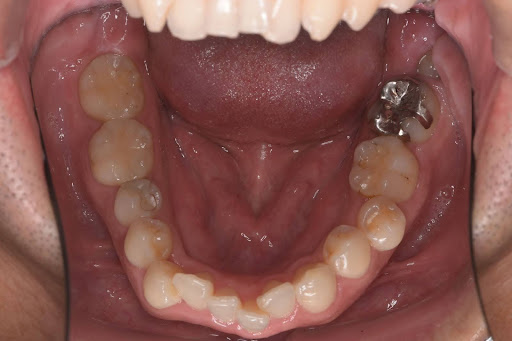

以下は症例写真です。

長年使用していた金属の詰め物を、生体親和性の高いセラミック素材に置き換えました。

天然歯のような透明感が生まれ、金属アレルギーの不安も解消されています。

<Before>

<After>